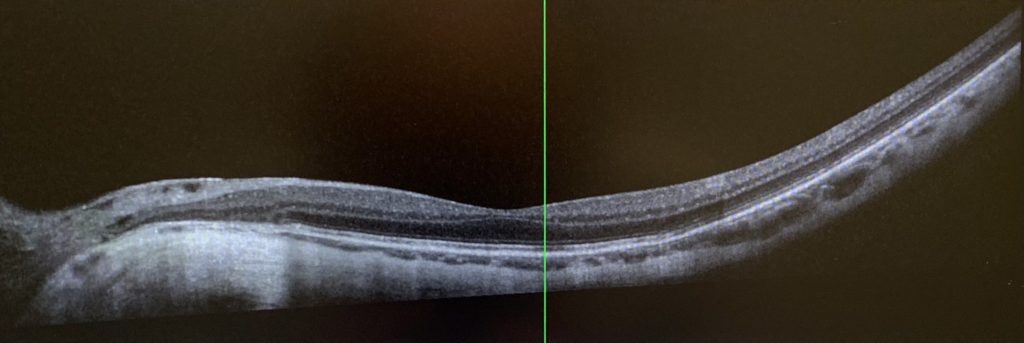

The day after the treatment, my symptoms continued to worsen, with my left eye’s vision becoming increasingly blurred and a shadow appearing in the upper left portion of my visual field. Although the Amsler grid test did not reveal any distortion, the black dot in the center of the grid would disappear when I moved my eye. During a follow-up examination at the clinic, my left eye’s vision had deteriorated further to 20/50. After reviewing the latest results from various specialized ocular tests and consulting with three retinal specialists in the clinic, I was ultimately diagnosed with uveitis.

After a comprehensive evaluation, Dr. Freund diagnosed my eye condition as punctate inner choroiditis, a rare form of multifocal chorioretinal inflammatory disease that can result in choroidal neovascularization. In light of my prior severe macular degeneration, this condition may significantly jeopardize my visual prognosis. Given the rapid progression of the condition, immediate treatment was necessary. Dr. Freund promptly prescribed an emergency medication plan and arranged for relevant laboratory tests, while also inviting a rheumatologist to participate in the consultation and join the treatment team